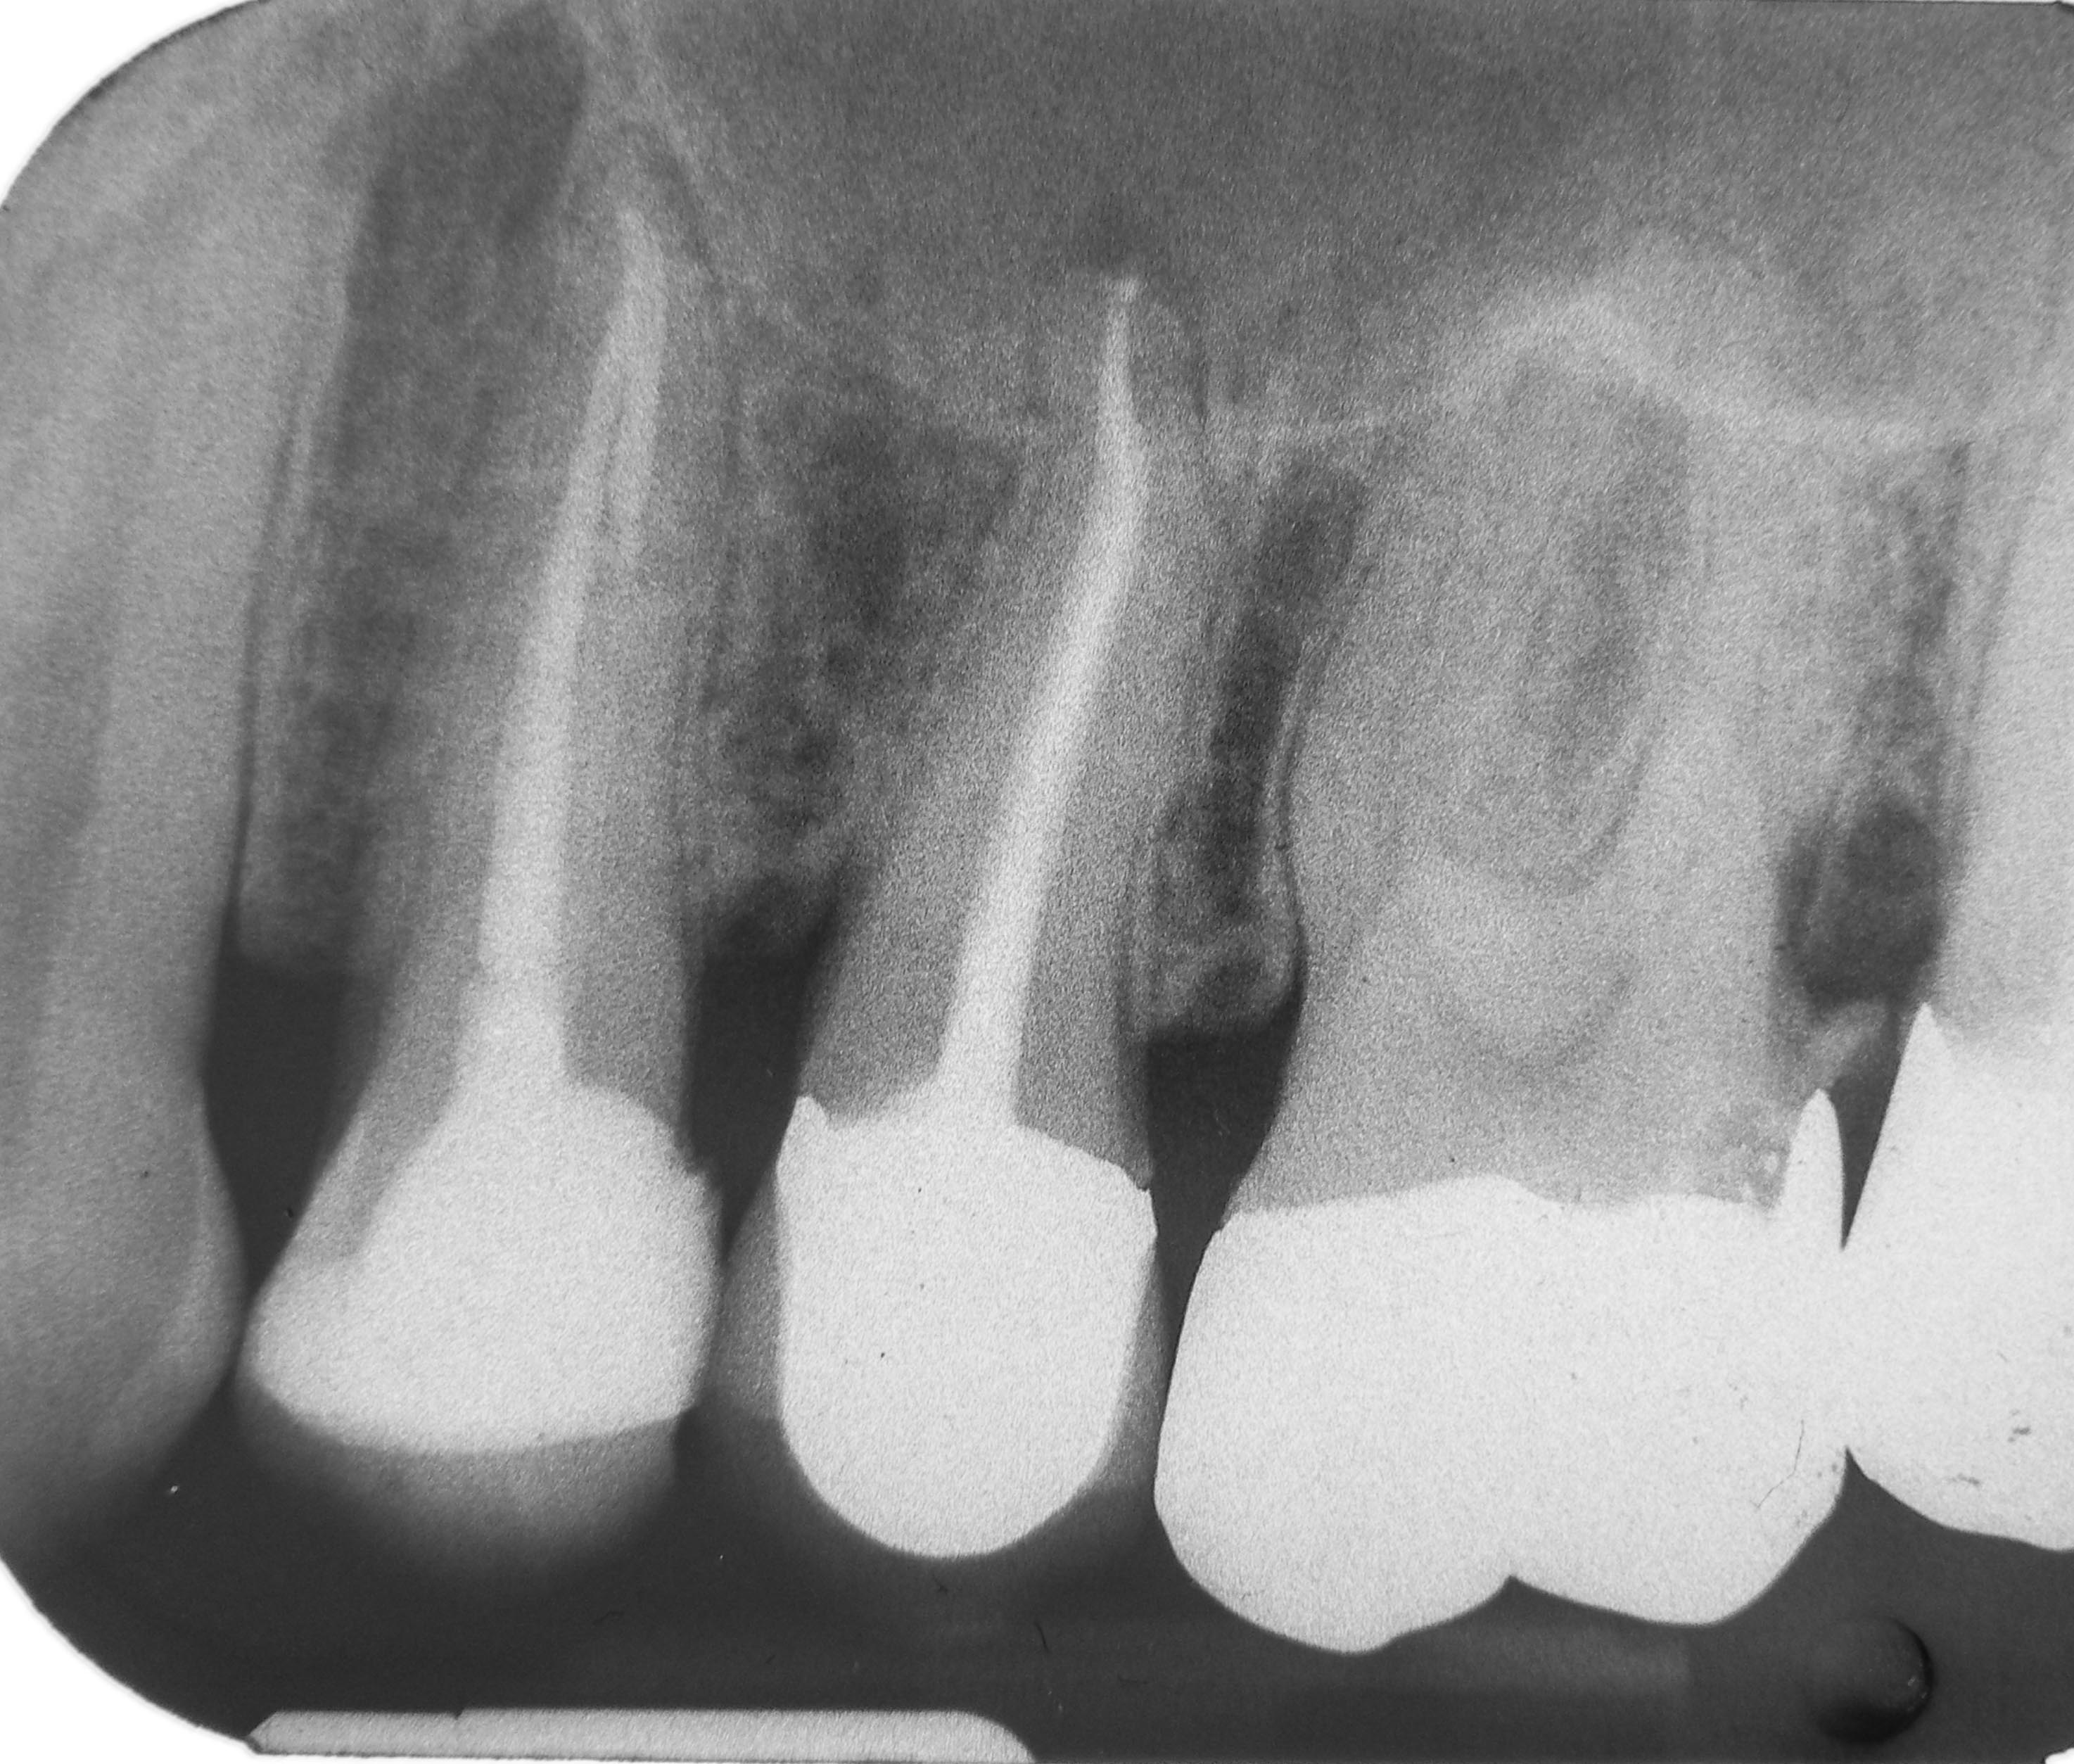

24 25 Verlaufskontrolle 2009 Veröffentlicht 4. November 2013 am 2948 × 2507 in „Chapeau“ oder der Wirt und die Wette 24 25 Verlaufskontrolle 2009